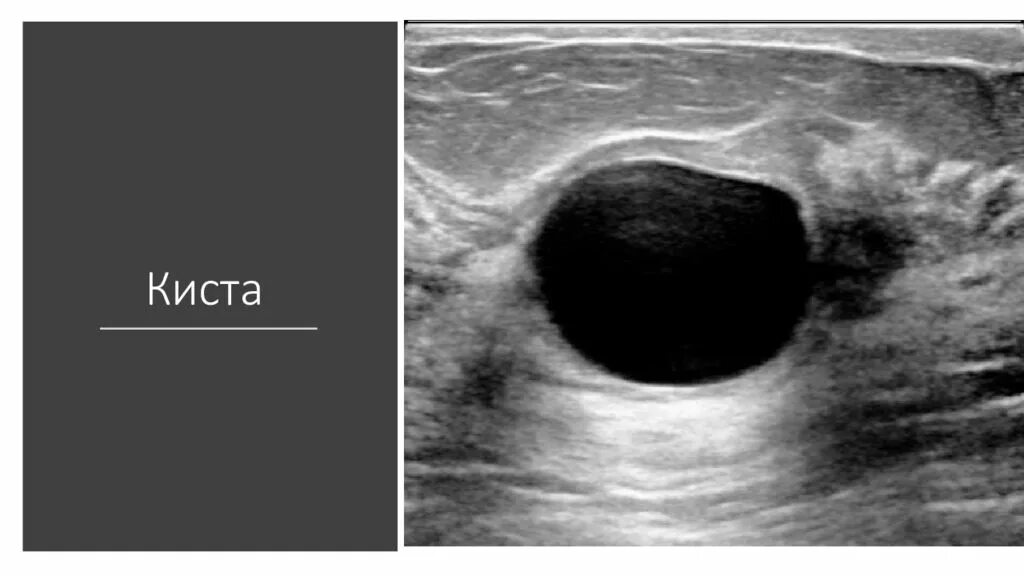

Содержимое кисты молочной